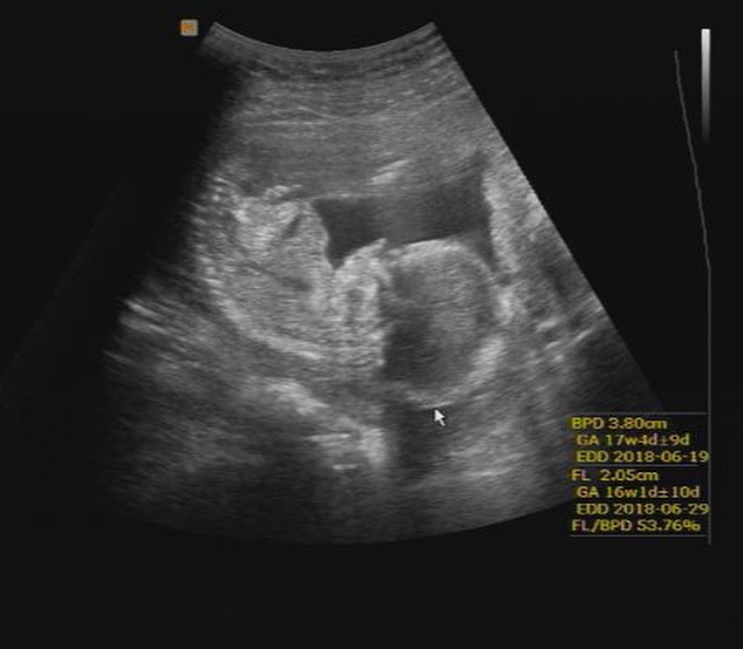

16 Haftalık Bebek Kaç Gram Olur

16 Haftalık Bebek Kaç Gram Olur.